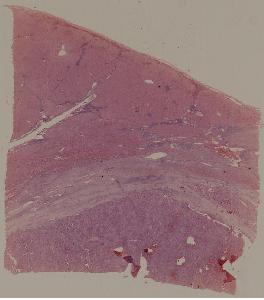

低倍视野

48.病毒性心肌炎

49.梅毒性主动脉炎

50.大叶性肺炎

51.肺肉质变

52.小叶性肺炎

57.肺癌

59.慢性萎缩性胃炎

60.胃溃疡

61.胃腺癌(胃粘液腺癌)

62.急性普通型病毒性肝炎

63.慢性活动性肝炎

64.急性重型病毒性肝炎

65.亚急性重型病毒性肝炎

66.活动性结节性肝硬化

67.非活动性结节性肝硬化

68.胆汁性肝硬化

69.肝细胞性肝癌

72.膜性肾小球肾炎

73.急性肾小球肾炎

74.新月体性肾炎